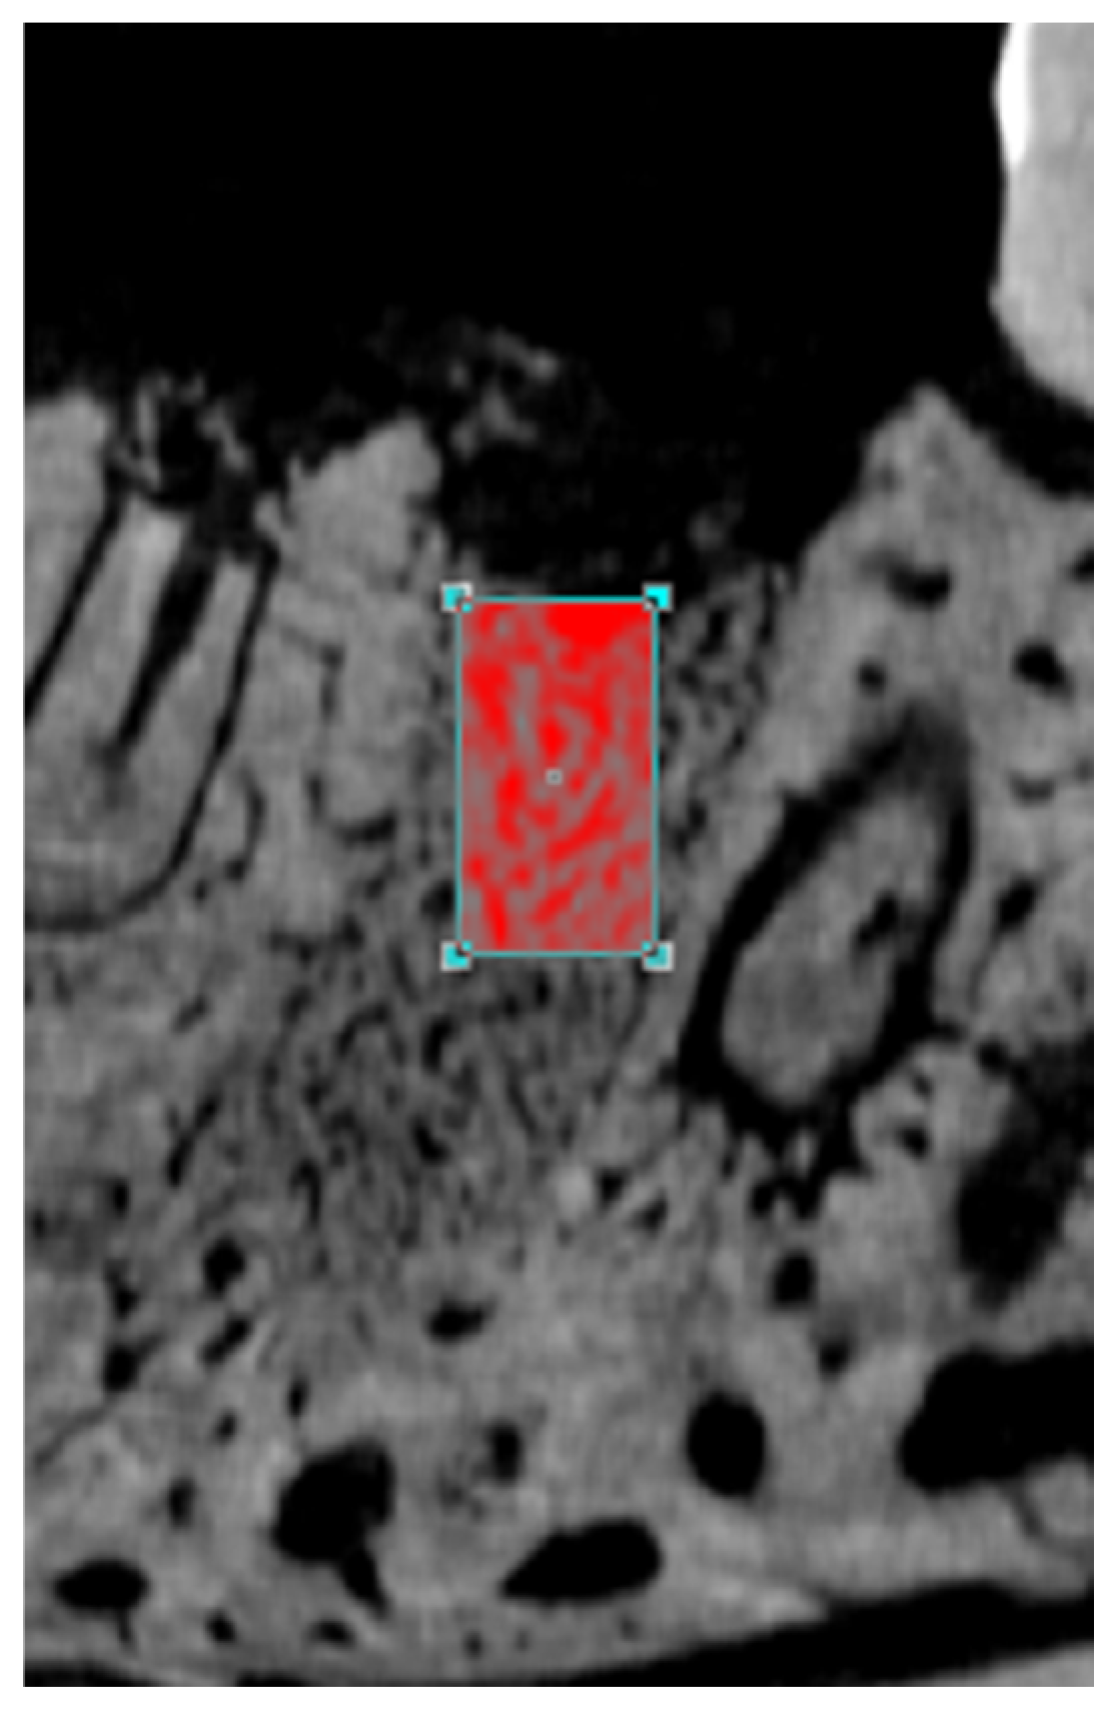

2.4.4. Microscopic Analysis and Microscopic Area of Interest (AMI)

2.4.5. Bone Tissue Histometry: Neoformed Bone Tissue (NFBT) and Non-Vital Bone Tissue (NVBT)